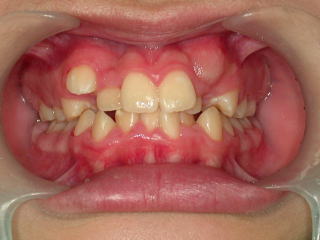

平成18年10月14日 だいぶそろってきました。